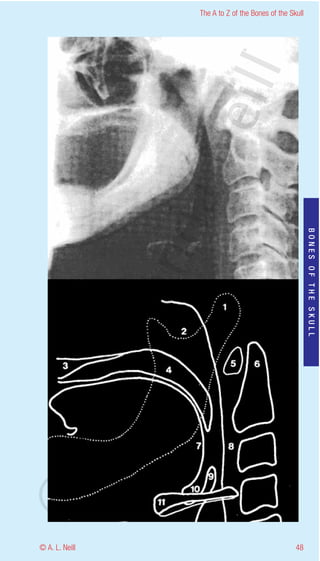

The A to Z of the Bones of the Skull

Mandible Lateral

eill

radiology

Showing relationship to surrounding soft tissue

1      Head of mandible – Condylar process

2      Neck of the Mandible

aN

3      Hard Palate

4      Soft Palate

5      Anterior notch of the Atlas (C1)

6      Odontoid process of the Axis (C2) – Dens

7      Posterior aspect of the tongue

8      Retropharyngeal sac

nd

9      Epiglottis

BONES OF THE SKULL

10     Vallecula - fold anterior to epiglottis

11     Hyoid bone